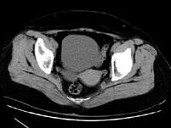

- 单项选择题女,27岁, 体检时B超发现右侧附件区囊性占位性病变,CT检查如图, 下列说法错误的是 ( )

A、病灶来源于右侧卵巢

B、病灶边界清晰

C、病灶为单房,壁薄,无分隔

D、考虑为卵巢浆液性囊腺瘤

E、考虑为卵巢囊肿